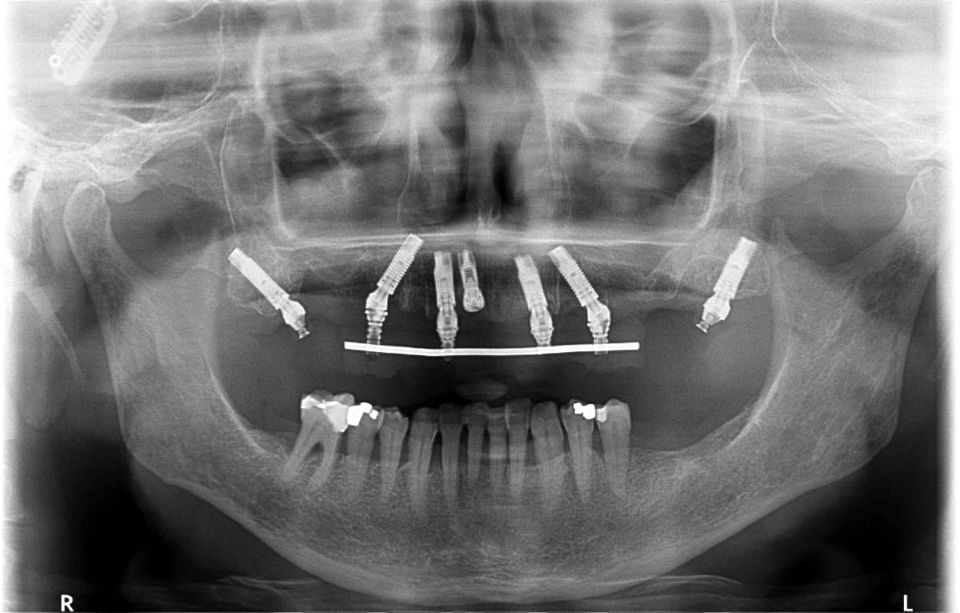

Del mismo modo ofrecemos cirugías implantológicas con flujo digital, utilizando férulas quirúrgicas personalizadas; permitiendo disminuir tiempos quirúrgicos y manteniendo la precisión en los tratamientos.

El Centre Odontològic Piñera dispone de un equipo radiológico de última generación que permite hacer Ortopantomografias (radiografías de toda la boca), CBCT dental y escáner dental intraoral en 3D (3 dimensiones). La exposición radiológica es mínima.

Esta tecnología favorece la rapidez en la exploración, así como la precisión en el diagnóstico y el consiguiente tratamiento.